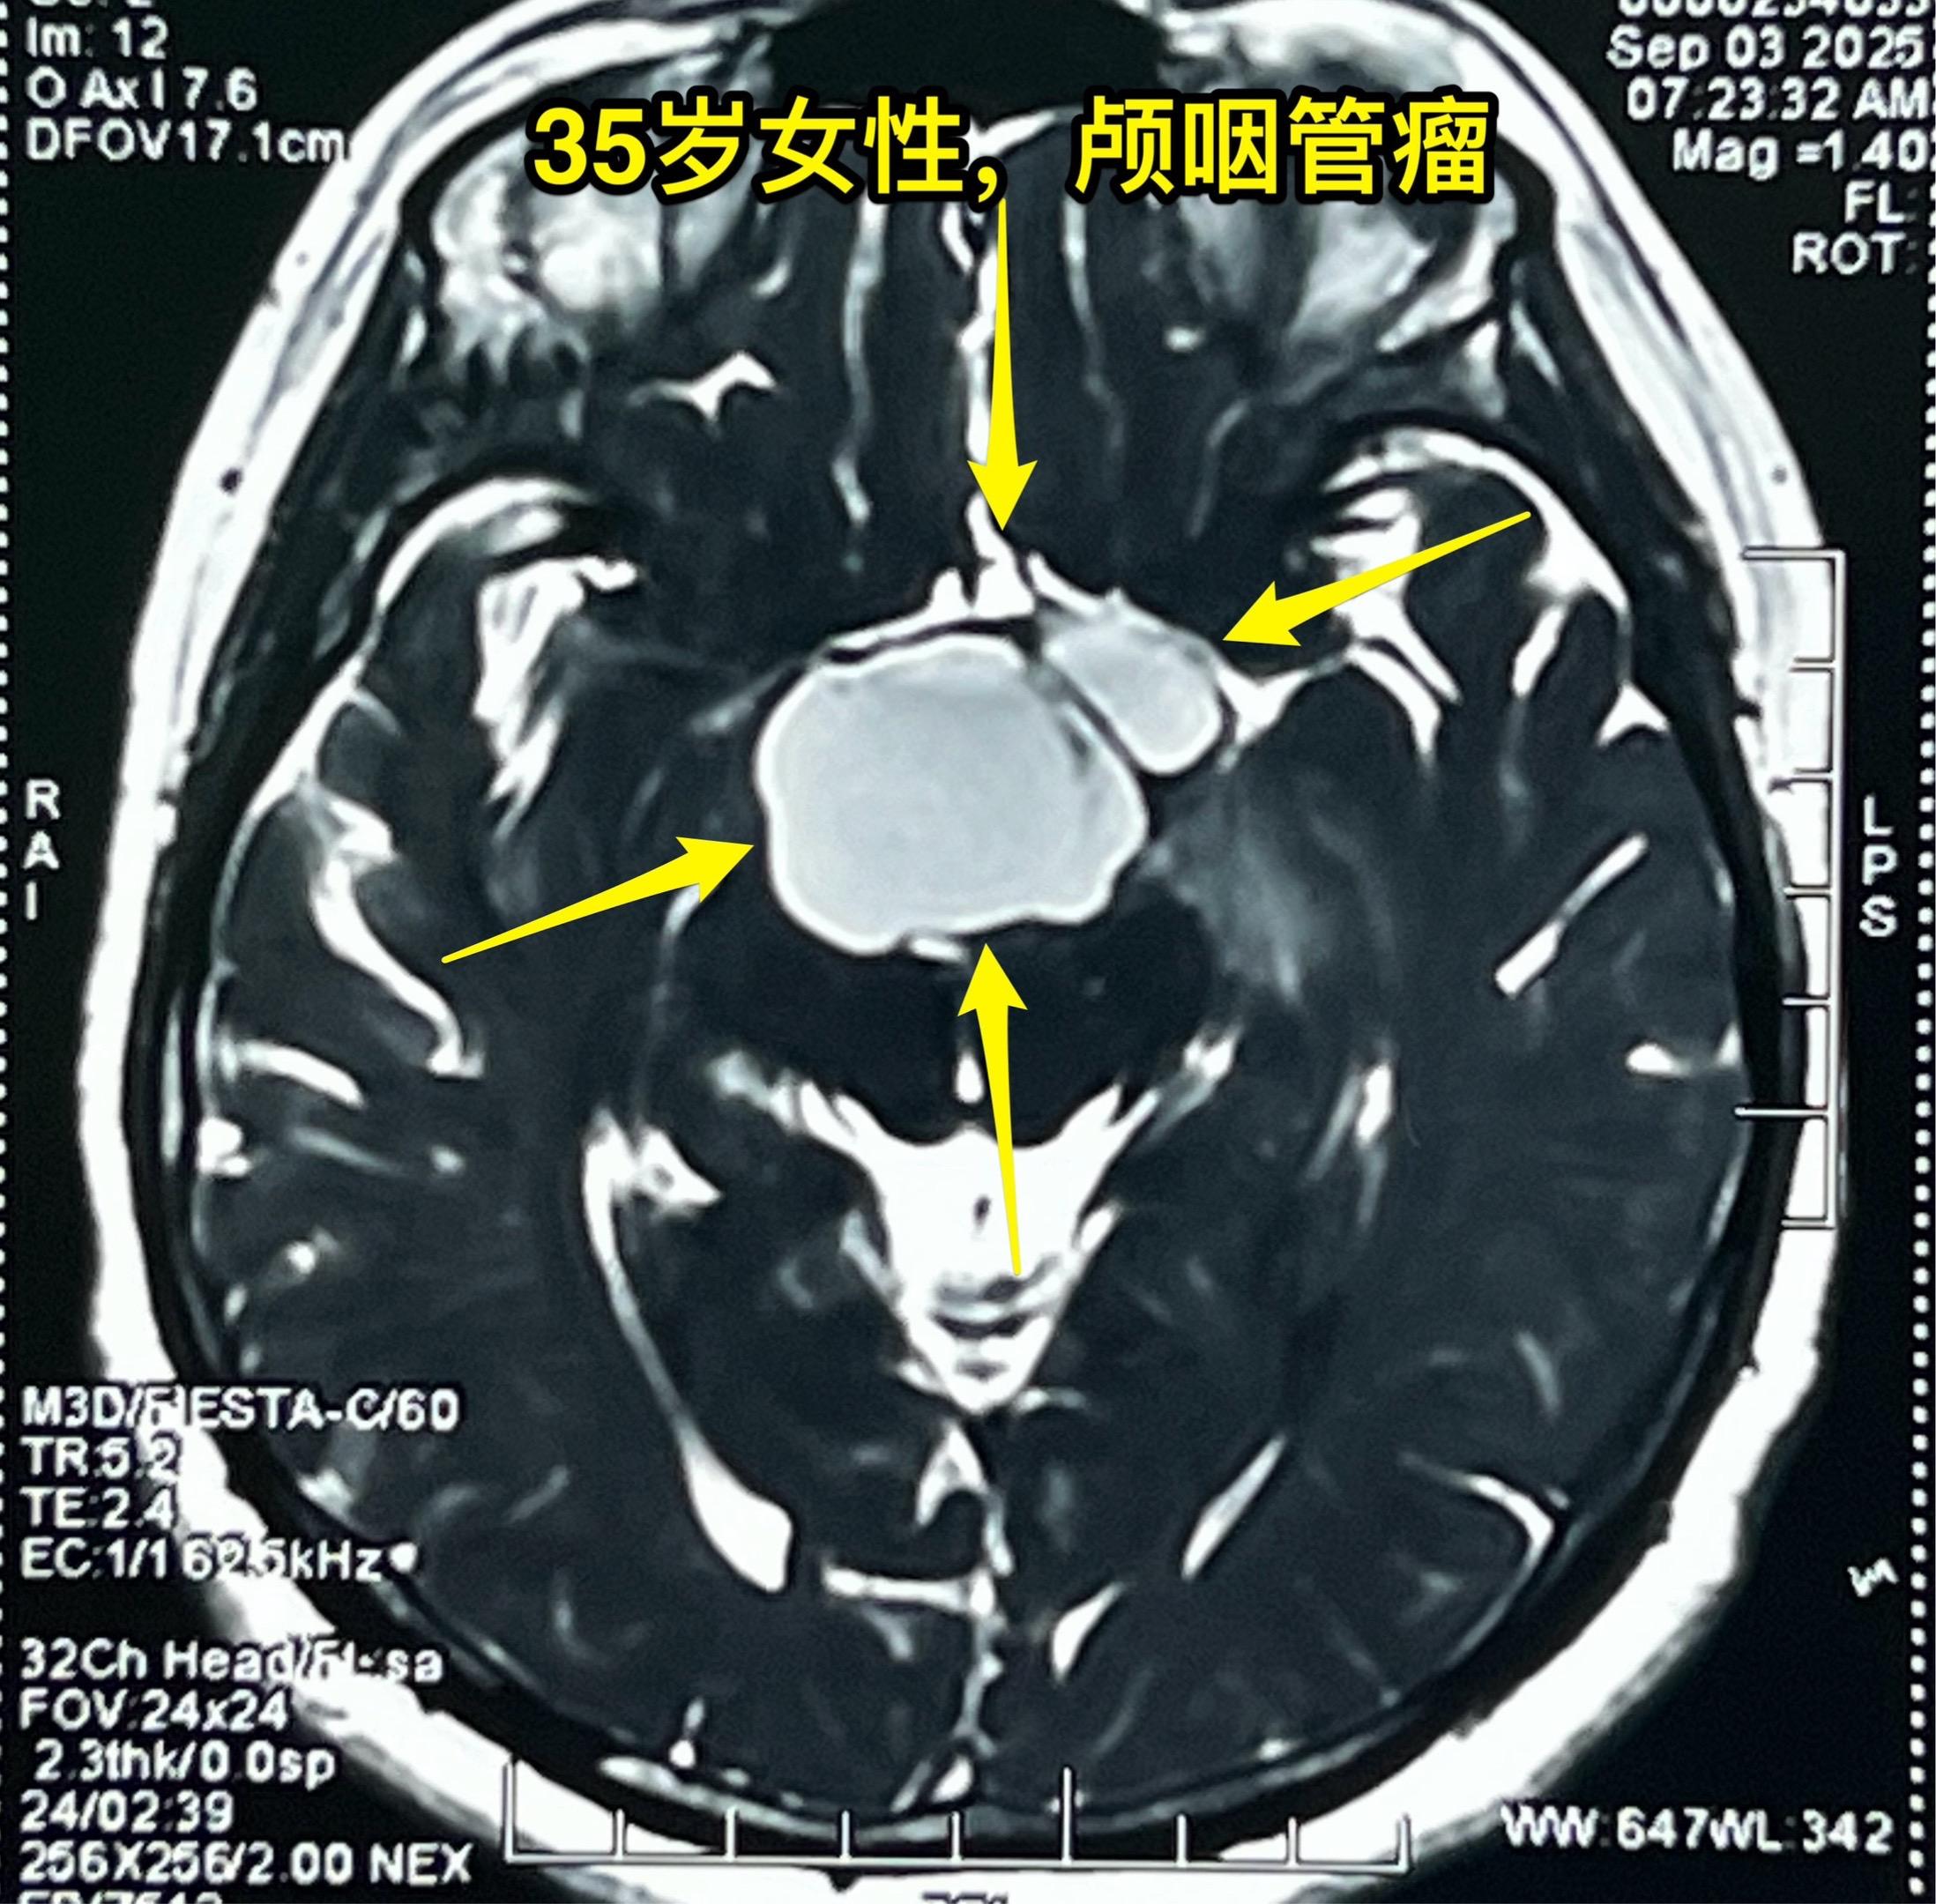

颅咽管瘤的症状科普。之前我多次讲过颅咽管瘤的症状,结合这个病人再说一次。 这个35岁女性在2025年8月发现了颅咽管瘤。 她两年前最开始出现生理周期紊乱、停经,这是下丘脑-垂体受损伤导致的内分泌系统功能障碍的表现。 一年前患者出现视力下降,越来越严重,一直到没有有效视力了才去就医,才发现这个颅咽管瘤。这是视神经-视交叉受到肿瘤压迫造成的。 在视力下降的同时病人出现长胖,体重显著增加。这也是下丘脑受损的表现。 病人在就诊